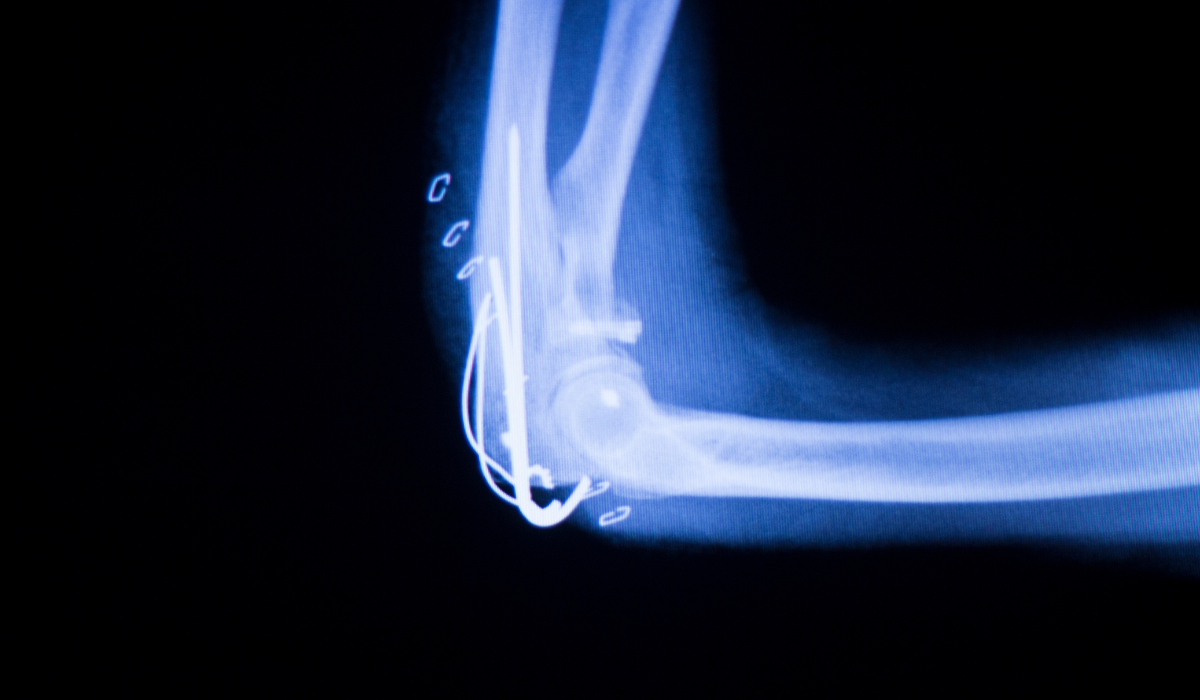

The elbow joint is a complex hinge joint formed where three bones meet: the humerus (upper arm bone), the radius, and the ulna (both forearm bones). This joint allows for two types of movement — flexion and extension (bending and straightening) as well as rotation of the forearm. Stabilized by muscles, tendons, ligaments, and cartilage, the elbow plays a crucial role in everyday tasks like lifting, throwing, and rotating the arm.

Yes, injuries, overuse, arthritis, or trauma can damage the bones, cartilage, or soft tissues around the elbow, potentially leading to pain, stiffness, or instability.